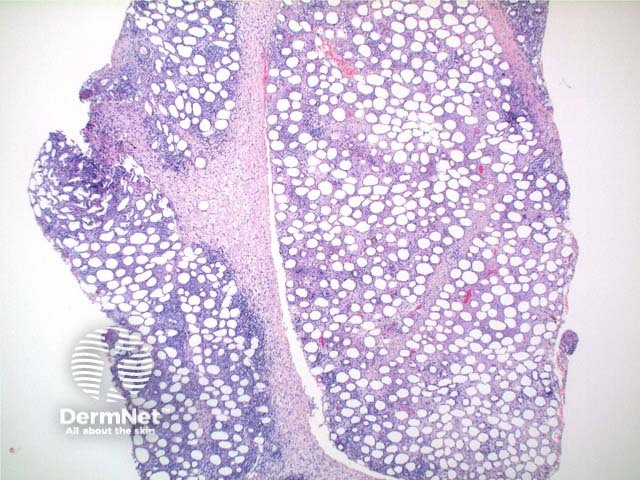

Scanning power view demonstrates lobular panniculitis (Figure 1). Relatively little dermal or epidermal involvement is seen (Figure 2). A dense infiltrate is seen predominantly within the fat lobules while some spillover into the septal panniculus may be seen (Figure 3). Germinal centre formation is rare. The infiltrate is predominantly lymphocytic with variable numbers of histiocytes engulfing nuclear debris (bean bag cells) and lipid (lipophages) (Figures 4 and 5). The lymphocytes demonstrate nuclear atypia and can be seen to characteristically rim the adipocytes (Figure 6).

Figure 1